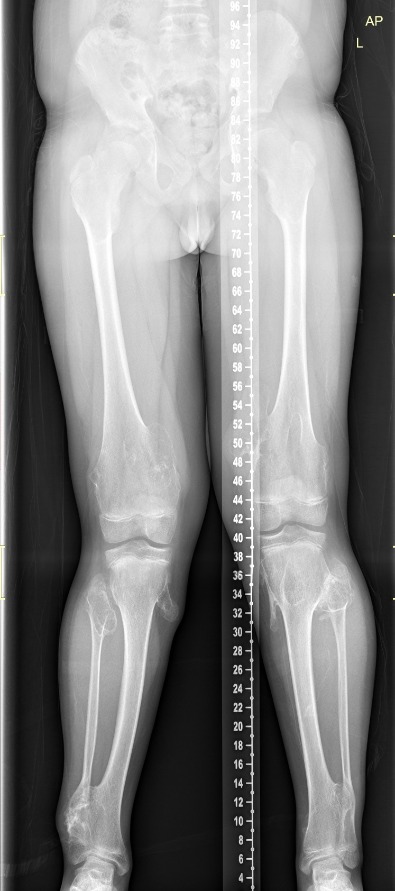

Πολλαπλά οστεοχονδρώματα

Οι εικόνες απεικονίζουν περιστατικό με πολλαπλά οστεοχονδρώματα, το οποίο χειρουργήθηκε από τον Δρ. Ζένιο.

Προ-εγχειρητικά

Μετ-εγχειρητικά